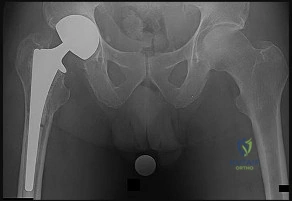

Question 26

During a surgical approach to the hip via the direct lateral (Hardinge) approach, the gluteus medius and vastus lateralis are split. To avoid iatrogenic denervation of the anterior portion of the abductors, the proximal split in the gluteus medius must not extend more than how many centimeters proximal to the tip of the greater trochanter?

The anterolateral (Watson-Jones) approach to the hip exploits the plane between the tensor fasciae latae (TFL) and the gluteus medius. Which nerve innervates both of these muscles?

Explanation

Question 61

A direct lateral (Hardinge) approach to the hip requires splitting the gluteus medius. To avoid iatrogenic denervation, the proximal split should not extend beyond what distance from the tip of the greater trochanter?